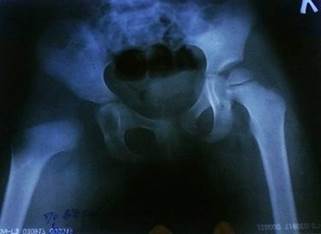

Вертлужная впадина: Важные моменты на УЗИ